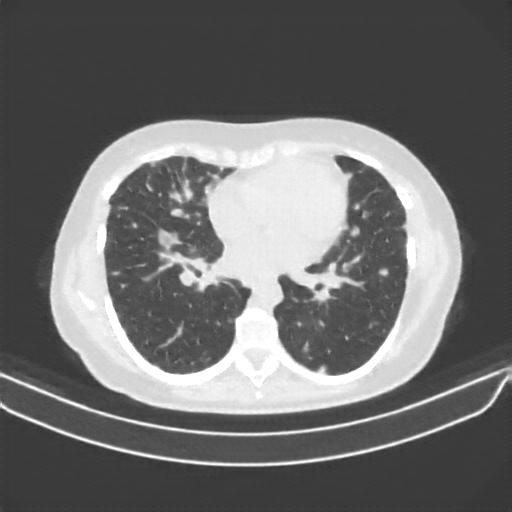

Generated VENOUS CT scan (A→B translation)

No window - Raw intensity values

Lung window (WL -600, WW 1500 β†’ Low βˆ’1350, High +150)

Targeted Slice 70 - Lung Window Analysis (Generated vs Real Venous)

0.752

Lung SSIM

110.9

Lung RMSE

46.5

Lung MAE

Average Lung Window Metrics Across All Slices (133 slices) - Generated vs Real Venous

0.749

Lung SSIM (Avg)

109.7

Lung RMSE (Avg)

44.6

Lung MAE (Avg)